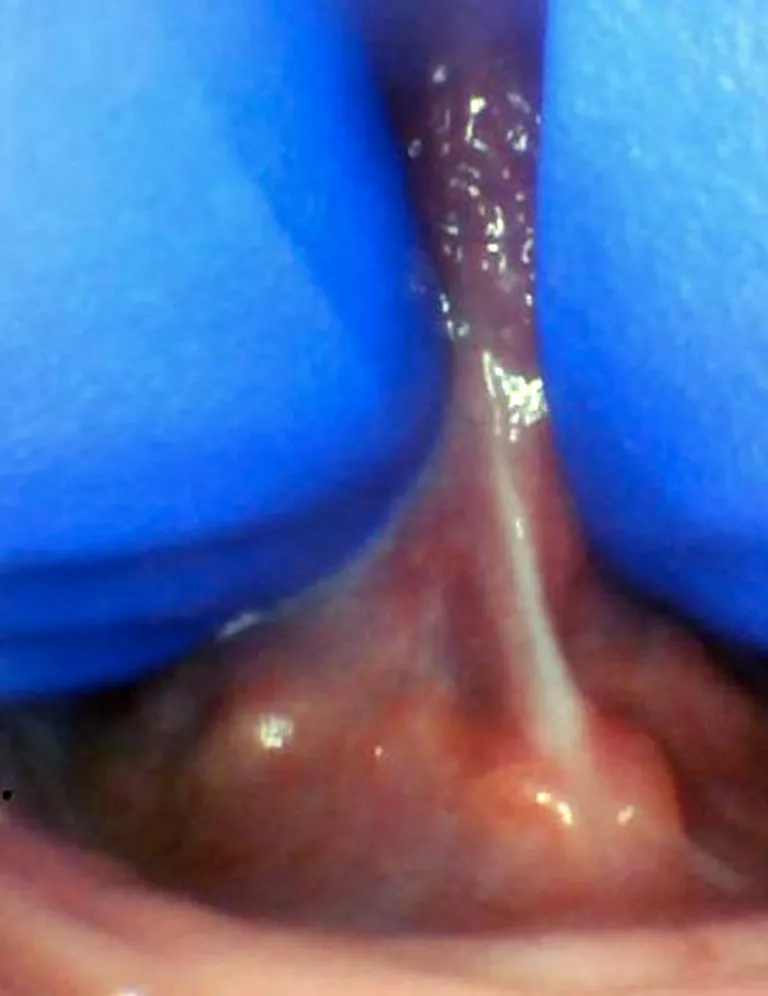

Enfant - Spectre de restrictions d'un FR lingual

Frein Restrictif Postérieur

Le frein restrictif postérieur ou sous-muqueux a été décrit récemment par Genna-Watson et Coryllos (2004), le terme est donc encore peu connu par les professionnels de la santé. Chaque frein possède une composante sous-muqueuse, mais ce type de frein est totalement sous-muqueux. Il est palpable et visible avec manœuvre et peut restreindre la mobilité linguale autant qu'un frein restrictif antérieur. Certains considèrent qu'un frein postérieur correspond également au frein de type 3 selon Kotlow (distal par rapport à la pointe de la langue, terme qui semblerait être préférentiel selon Kotlow afin d'éviter toute confusion). D'autres considèrent que l'appellation est fausse, cependant, ce débat a lieu d'être en Amérique où l'on parle de "langue attachée postérieure", ce qui d'un point de vue anatomique porte à confusion, la partie postérieure de la langue étant la base de la langue. En France, il n'y aurait a priori aucune raison de penser que l'utilisation de ce terme est faux - cependant, de nombreux professionnels semblent encourager les praticiens à parler de mobilité antérieure (TRMR-TIP) ou postérieure (TRMR-LPS) impactée par un frein restrictif (ou autre, cf partie Diagnostic), et non de "posterior tongue-tie" ou "anterior tongue-tie".